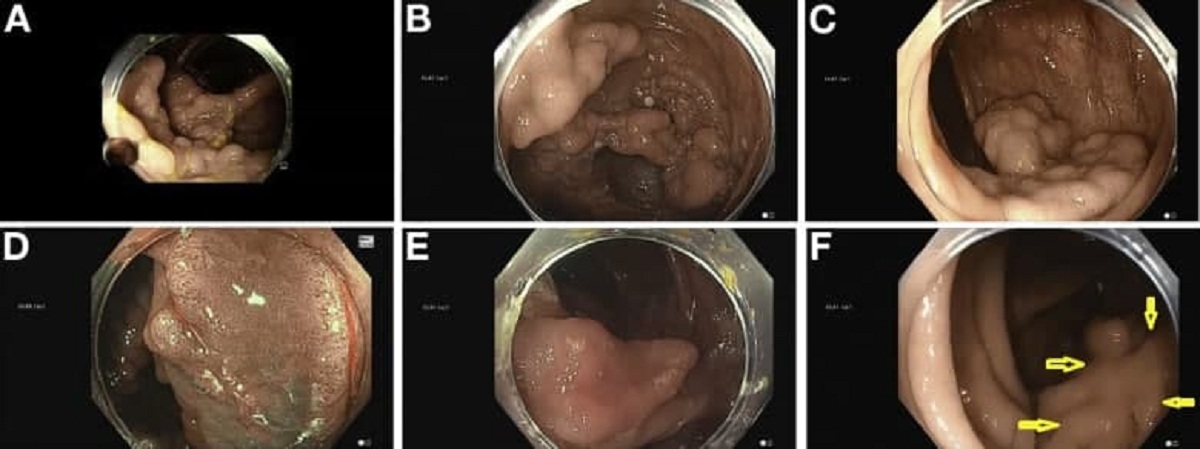

- Үзүүртээ бичлэг хийх боломж бүхий камертай урт гуурсан хоолойг бие дотор оруулан ходоод болог бүдүүн гэдэсний салстыг дотор талаас хэсэгт харж шалгадаг шинжилгээ юм.

- Ходоод болон бүдүүн гэдэсний дуран гэсэн үндсэн 2 төрлийн дуран байдаг ба ходоодны дурангийн шинжлгээгээр улаан хоолой, ходоод, дээд гэдэсний салтын бүтцийг харин бүдүүн гэдэсний дурангийн шинжилгээгээр бүдүүн гэдэсийг бүхэлд нь мөн цутгалан салстын төгсгөлийн хэсгийн салстыг үнэлэн эмгэг бүтцийг илрүүлж болох хамгийн оновчтой шинжилгээ юм.

- Монгол улс нь хоол замын өвчлөл болон нас баралтаараа дэлхийд дээгүүр байрыг эзэлдэг ба дурангийн шинжилгээ нь ходоод, улаан хоолой, бүдүүн гэдэсний өвчин болон хавдрыг эрт үед нь илрүүлэх хамгийн найдвартай, оновчтой цорын ганц оношилгоо юм.